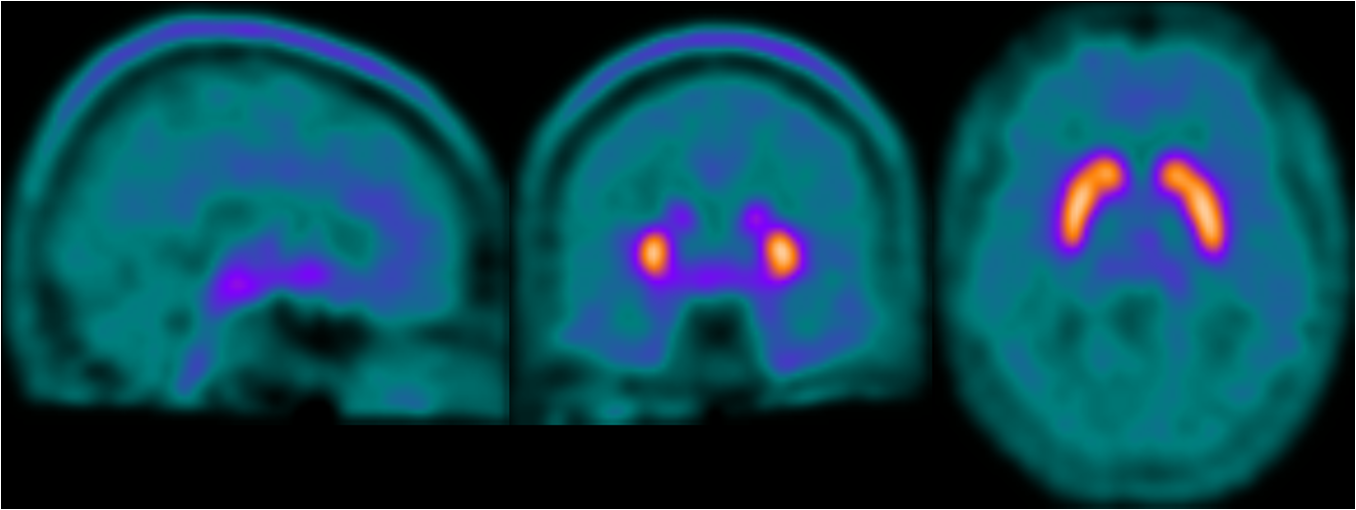

Following the meeting with Giovanna to review the first version of the FDOPA PET Imaging leaflet, Gill worked on the revisions needed to create the second version. Giovanna had provided three different photographic images of PET scans:

Gill experimented with drawing the rainbow colour-scheme and the blue-green colour scheme PET scans, as the red colour scheme is not as visually appealing and would not work as well with the existing illustrations. The scans will have to be placed on a black background (as in the header image of this post) to look their best, and to match how the scan results appear in the PET imaging software.

Gill then revised the text to even out the line lengths and adjust spacings. As the PET scans require a black background, Gill extended that down from the title bar. This black are does help to separate the first two sections of the text from the third section, although the layout will probably need more work. Gill added the blue-green PET scan illustrations, although the colours can be changed – it may be worth including some red to tie-in with the KCL logo and the elapsed time image. She also added the blue-green PET scan images to the screens in the radiographer illustration.